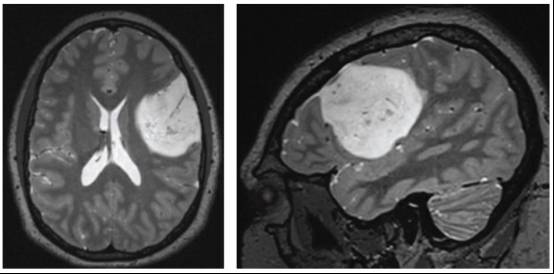

通常首选CT扫描或磁共振(MRI)影像学检查。根据患者首次就诊地点不同(急诊科,住院或门诊)选择对应的检查方式。MRI平扫+增强扫描可以精细的显示和评估肿瘤的范围和对比剂的摄取情况。明显强化常提示更高级别的胶质瘤。

低级别胶质瘤(尤其是II级胶质瘤)一般不强化。但毛细胞性星形细胞瘤(一种低级别的囊性星状细胞瘤)可出现增强的壁结节。视神经通路胶质瘤是一种弥漫浸润性低级别胶质瘤,可引起视神经,视交叉或视束增粗,往往伴有不同的增强表现。与高级别胶质瘤完全不同,血管源性脑水肿不是低级别胶质瘤的主要特征。

图2. 基底部位于皮层且无增强的低级别胶质瘤的典型影像学表现。 MRI T2加权像上表现为高低混杂信号并伴有点状钙化,这符合少突胶质细胞瘤的诊断。